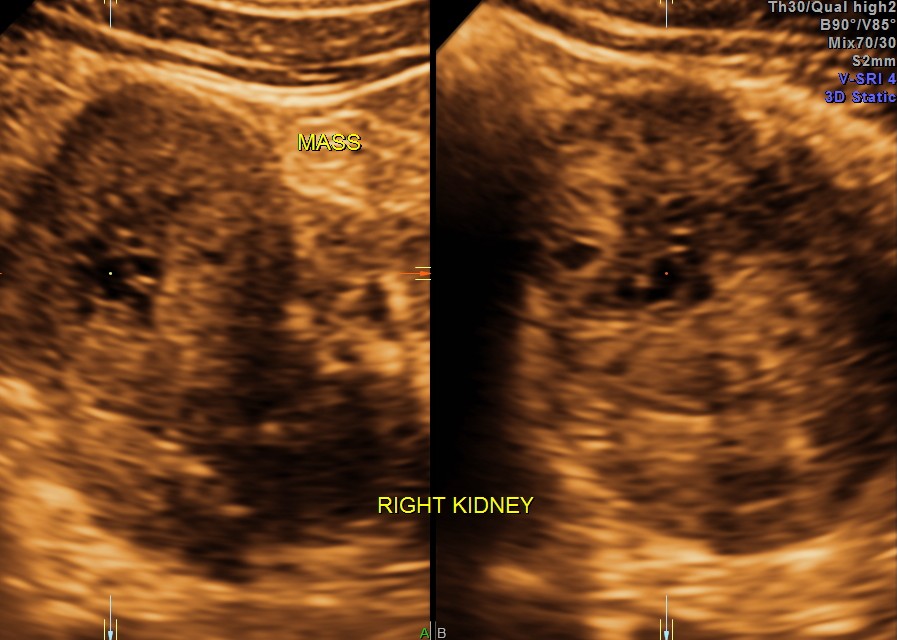

3 D images are given below.

the next is a reconstructed image of the mass.

The ultrasound diagnosis was a right renal mass – likely to be hypernephroma.

The images are presented to show the increased vascularity on colour Doppler and the lobularity seen in the reconstructed image and also for the clinical presentation of pain on the contralateral side due to herpes zoster.